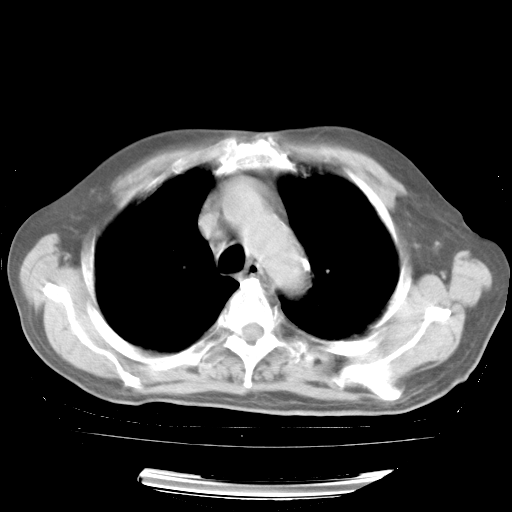

4月28日肺部CT